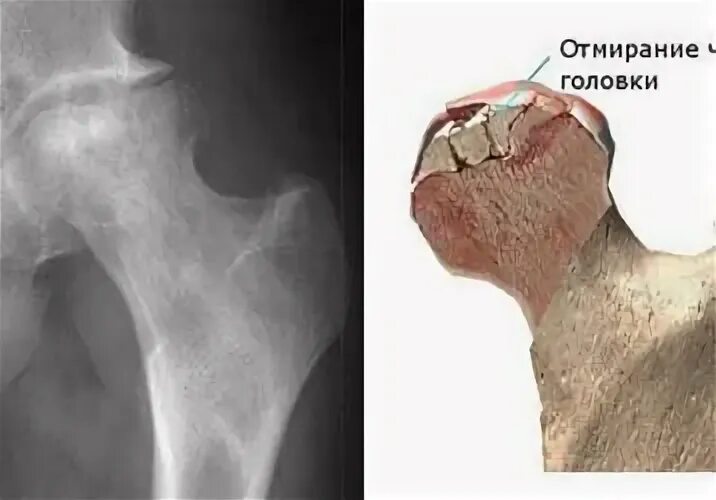

Боли при некрозе тазобедренных суставов